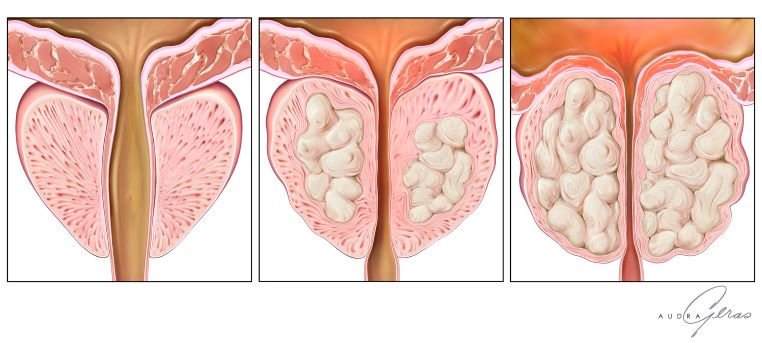

Фіброзні зміни передміхурової залози: що це таке? Фіброзні зміни передміхурової залози — проблема, яку важливий не оминути. Чому? Та тому що це дещо серйозніше